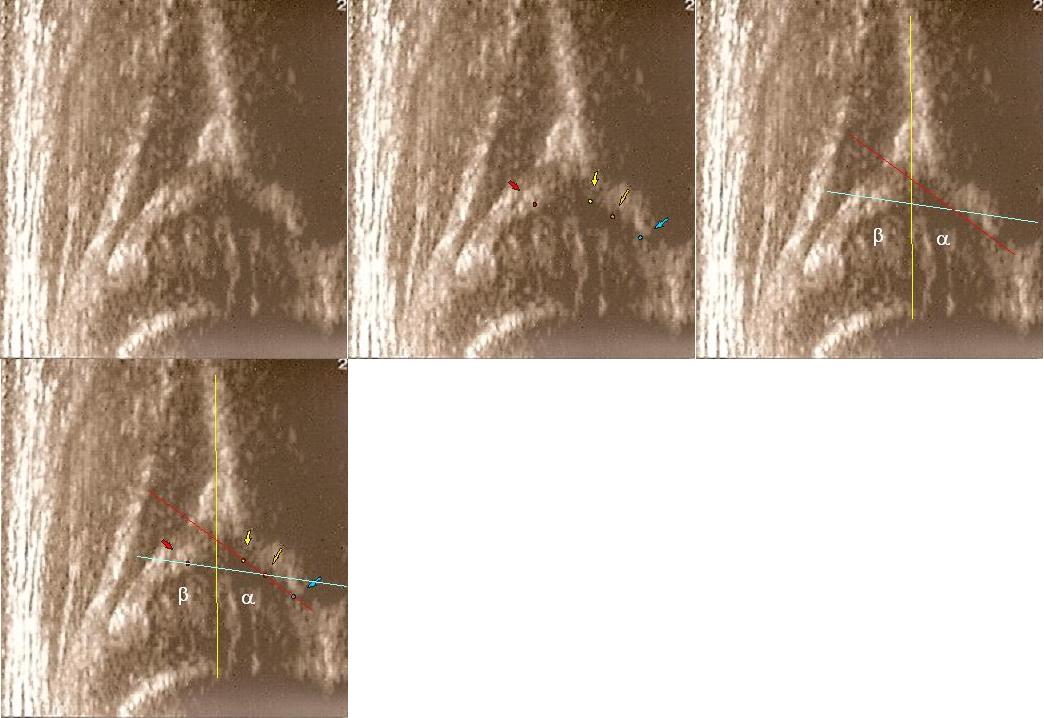

typ II/D gdolny kąt @ 48st kat B 85;

dach kostny bardzo niewystarczajacy;brzeg kostny spłaszczony ;dach chrzestny przesunięty dogłowowow ( szczyt głowy jest poniżej szczytu dachu chrzęśtnego)

dolne zdjęcia strzałki pokazują obrabek(czerwona):brzeg kostny (żółta);gałąż dolna(niebieska) ,

prawidłowy przebieg linii dachu kostnego(niebieska) stycznie do echa gałęzie dolnej i echa brzegu kostnego ;

linii dachu chrzęstnego (czerwona) stycznie do brzegu kostnego i przez środek geometryczny obrąbka i

linii podstawnej ( żółta)równolegle do sylwetki kości biodrowej po zewnetrznej stronie prze punkt gdzie ochrzęstne przechodzi w okostna

i styka sie z echem kości

typ II/D powyżej żle wykreślony jak typ I ( kąt @ 62st kat B 55)trzeba uwazać ,podstawą oceny jest wygląd stawu podczas badania kąty tylko potwierdzaja rozpoznanie, w przypadku rozbieżności wygląd stawu decyduje nie kąty

typD

kąt @ 48st kat B100;